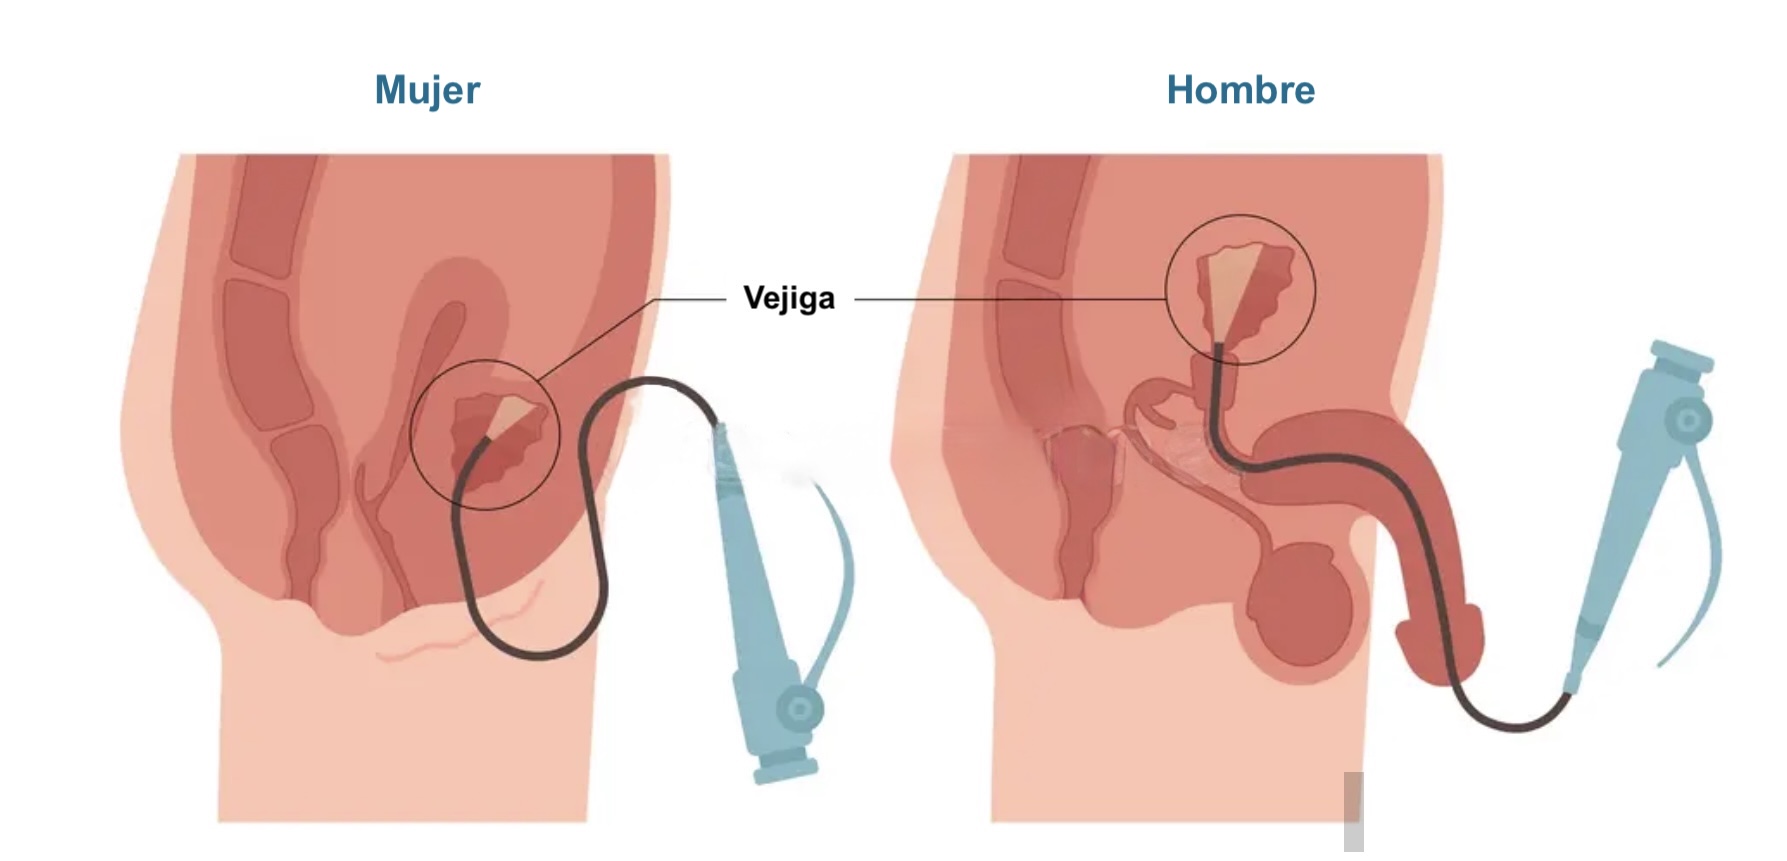

La uretromeatotomía es un procedimiento quirúrgico ambulatorio que se realiza para ampliar el meato uretral y el segmento distal de la uretra cuando existe una estrechez que dificulta la salida normal de la orina 🚻

🏥 ¿Cómo se realiza?

- 1902062: Uretrocistoscopía.